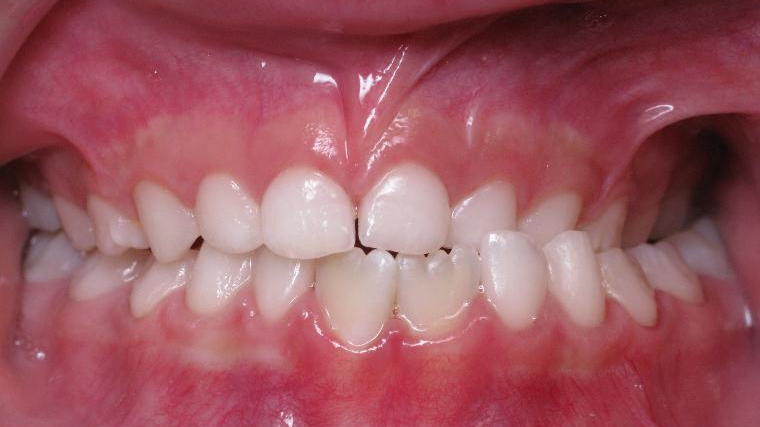

bilan début et fin de traitement

inversion des dents posterieur cote gauche